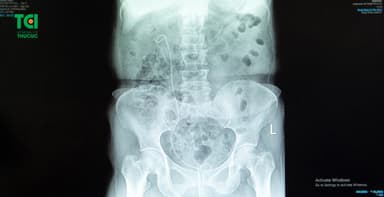

Trong hệ tiết niệu sẽ gồm các cơ quan bài tiết, vận chuyển, chứa và đào thải nước tiểu ra khỏi cơ thể, gồm: thận, niệu quản, bàng quang và niệu đạo. Sỏi tiết niệu là sỏi hình thành ở một trong bốn cơ quan ở hệ tiết niệu.

Sỏi tiết niệu có thể đa dạng về kích thước, chủng loại, vị trí, số lượng… Sỏi từ 5mm trở xuống được đánh giá là sỏi nhỏ và có thể can thiệp để sỏi tự đào thải qua đường tiểu. Sỏi từ 6mm trở lên cần điều trị ngoại khoa theo chỉ định hoặc mổ mở lấy sỏi. Mỗi vị trí sỏi khác nhau sẽ điều trị theo phương pháp khác nhau, tùy vào thể trạng của bệnh nhân.

Sỏi tiết niệu là sỏi hình thành tại thận, niệu quản, bàng quang và niệu đạo của người bệnh